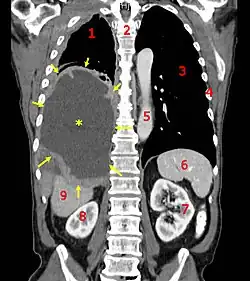

| CT scan showing a left sided mesothelioma with an enlarged mediastinal lymph node | |